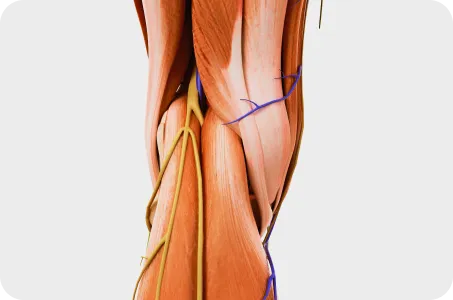

겉모습만 보지 않습니다.

속까지 볼 줄 알아야 진짜 전문가입니다.

내부 장기의 무력과 긴장, 틀어짐이 체형의 틀어짐을 유발합니다. 예를 들어, 우측에 위치한 간이 아래로 처질 경우, 우측 어깨가 따라서 처지게 됩니다. 연산당당한방병원은 대학병원급 CT, MRI 장비를 통해 내과 전문의와 협진하여 숨어있는 내장기 문제까지 진단하고 치료합니다.

Skin rolling 근막 검사

근막이완 롤핑요법